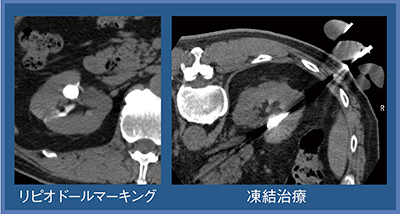

症例2(60歳代,男性)は両側腎癌で,左腎は部分切除,右腎は凍結療法となった。単純CTではわかりにくかったため,リピオドールマーキングを行って治療を施行した(図4)。治療3か月後の経過観察では,部分切除部は瘢痕化,凍結部は腫瘍濃染が消失し,収縮性変化が認められた(図5)。

図4 症例2:両側腎癌,右腎に対する凍結療法(60歳代,男性)